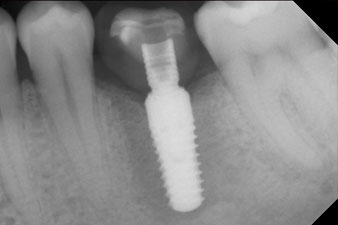

Fig. 10: The x-ray check shows the success of the osseointegration and the crown screwed in position without a gap.